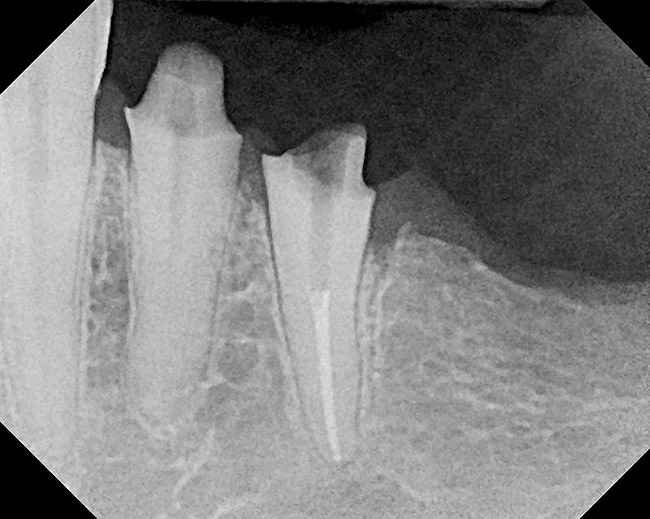

Figure 14  The preoperative radiograph showed an overhanging margin that was in close proximity to the bony crest.

Figure 14

Figure 16  After initial positioning of the bone, keeping the tip of the laser in intimate contact with the root surface, a slight troughing of the bone was seen on radiographic examination.

Figure 16

Figure 18  Radiographic examination after smoothing and blending of the bony surfaces confirmed that the bone was smooth and the ledge was eliminated.

Figure 18

Figure 22  Radiograph taken 8 weeks after closed-flap resective surgery was performed. Note that the bony contour was good, but some minor unevenness was apparent.

Figure 22

Figure 23  Radiograph taken 6 months after resective surgery and placement of the definitive prosthesis. Note how the bony crest remodeled and was much smoother than seen in the 8-week postoperative radiograph. By making the surgical correction using the closed-flap technique at the time of preparation and impression taking, a significant amount of operative time (> 6 months) was saved and an excellent biologic result was achieved.

Figure 23